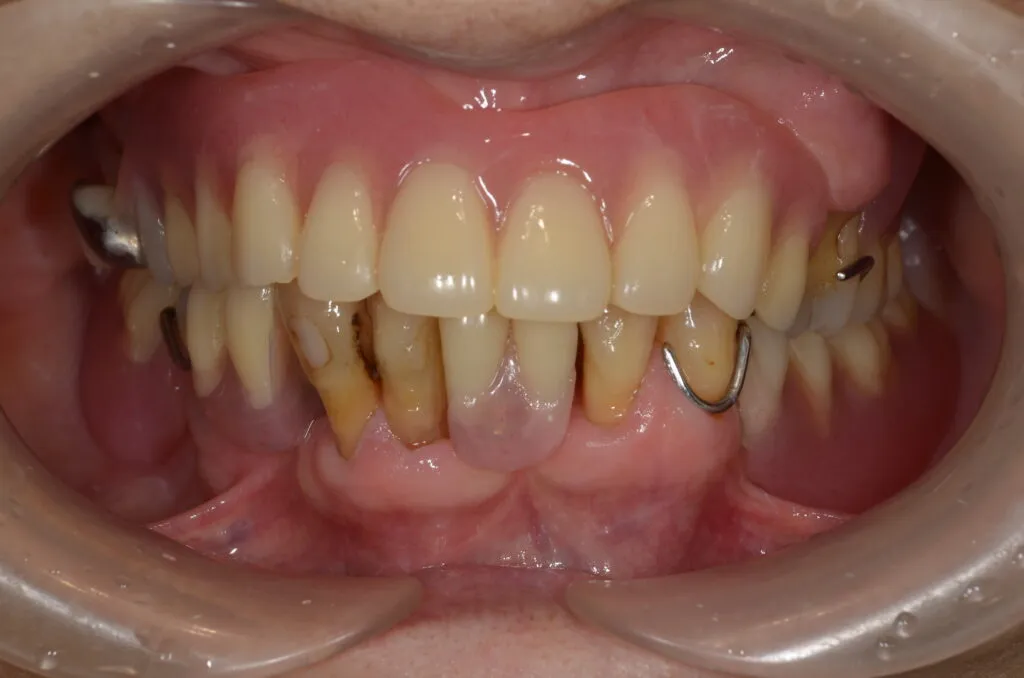

こちらの患者様の場合

【期間】2ヶ月

【費用】¥350,000~¥450,000/片顎(税抜)

【デメリット】精密に製作するため、保険の入れ歯よりも回数・費用がかかります。

上の写真は当院で上下総義歯を作製された患者さんです